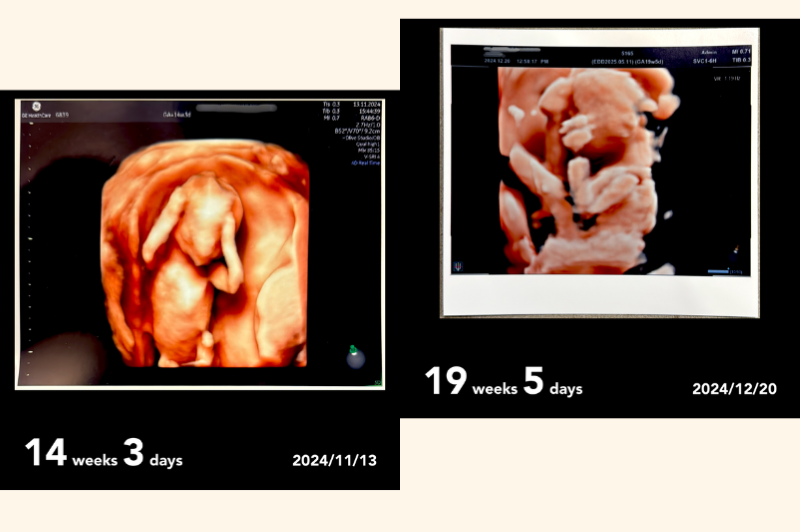

おなかの赤ちゃんは元気に育ってくれています。

安静を指示されるなど心配も多い妊娠期間でしたが、いよいよ出産にむけてもカウントダウン。ようやく少し、安心できるかなとホッとしています。